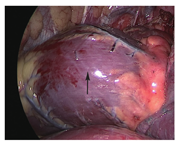

患者男性,45岁,因"查体发现肺部阴影9个月"于2019年12月10日入院。患者自诉无明显不适,未行系统诊治。既往无特殊病史,无家族性疾病史。入院查体:血压:129/74 mmHg,心率:59次/min,窦性心律,律齐,触诊心尖搏动位于胸骨左缘第五肋间锁骨中线,听诊双肺呼吸音清,未闻及干湿性啰音,各瓣膜听诊区未闻及杂音。入院12导联心电图示窦性心动过缓,心率59次/min,ST-T改变(图1)。胸部X线片示心脏左偏,主肺动脉间无肺组织影,左肺毛玻璃影(图2A);胸部CT未见心包影,左肺上叶多发毛玻璃结节(图2B)。超声心动图未见明显异常。术前诊断:肺部结节,遂行胸腔镜下肺部结节切除术。术中患者右侧卧位,取左胸第4肋间、腋中线第7肋间作为腔镜入路,探查见胸膜无粘连,完全性心包缺如(图3),行左肺上叶切除术。病理诊断:以贴壁生长为主的肺泡上皮源性肿瘤,微浸润性腺癌(2 cm×1.6 cm),原位腺癌(0.8 cm),均未侵及脏层胸膜,未累及支气管断端。肺癌多基因检测:EGFRExon21 L858R阳性突变。术后诊断:肺部占位,先天性心包缺如。复查超声心动图:右室前壁、剑突下右室游离壁未见心包样回声,右室前壁活动度明显增大。术后6个月随访,患者胸部CT未见新发病灶、无胸腔积液,无明显临床症状。

胸腔镜下见心脏裸露,未见心包,为完全性心包缺如裸露心脏

据文献报道,大部分病例为无症状,部分是在与心脏其他相关症状的鉴别诊断过程中确诊的,如不典型的心前区的刺痛或左侧的胸痛、呼吸困难[7,8]。本病例即在行肺部病损切除术中发现并确诊,图3为术中胸腔镜所见,可见心脏裸露,无心包包裹。除了部分性心包缺如导致的心肌嵌顿外,其他类型完全性心包缺如产生疼痛的机制尚不能明确。心包缺如最紧急、最严重的表现为左侧心包部分缺如引起左侧心肌的绞窄导致的猝死,目前已有3例报道[1,9,10]。